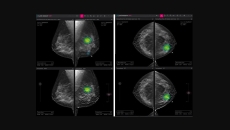

mammography

The company develops AI tools to analyse chest x-rays and breast mammography.

The company has developed a line of products targeting the mammography space to enable early and accurate breast cancer detection.